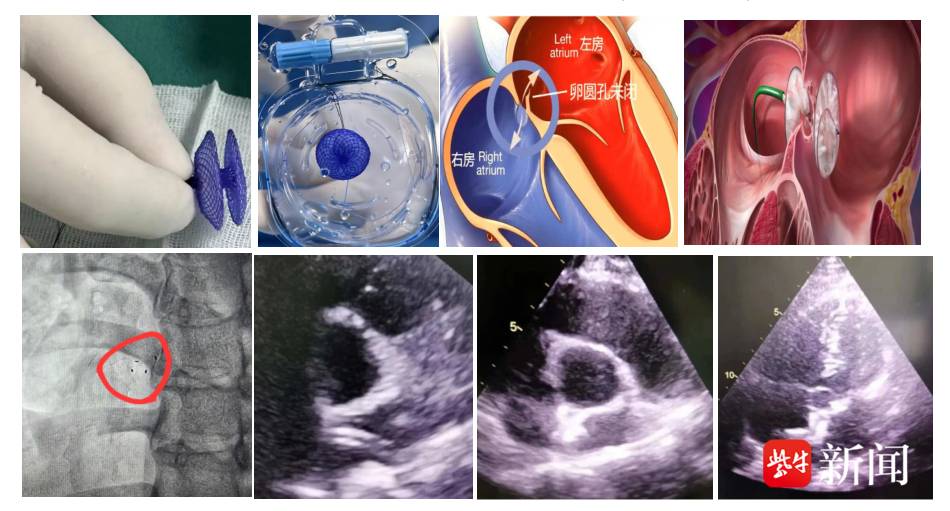

近日,镇江瑞康医院心血管内科介入团队成功为一名深受偏头痛困扰的年轻女性患者,实施了生物可降解卵圆孔封堵器植入术。此项新技术的成功开展,标志着该院在结构性心脏病介入治疗领域进入了“介入无植入,植入无残留”的崭新阶段,为众多卵圆孔未闭(PFO)患者提供了更优的治疗选择。

16日,院方介绍,该名年轻女性因长期反复头痛,在外院超声发泡试验(右心声学造影)强阳性,遂慕名至镇江瑞康医院心内科就诊。入院后经食道超声显示卵圆孔回声分离1.2 mm,明确诊断为“卵圆孔未闭(PFO)”,这正是导致她顽固性头痛的“元凶”之一。

与传统金属封堵器不同,本次手术采用的MemoSorb生物可降解封堵器是由聚对二氧环己酮(PDO)和聚乳酸(PLA)等生物材料制成,在成功封堵缺损后的数月内,会像“可吸收缝合线”一样逐步降解为二氧化碳和水,并通过人体新陈代谢完全排出体外,最终仅在心脏缺损处留下患者自身的修复组织。

手术在DSA和超声影像学双重定位下开展。生物可降解封堵器在超声下清晰可见,但在DSA下的显影有限,仅可见左右盘面及腰部分布的4个梅花样显影点,这就要求手术医师具备更高的操作技能和精细度。

术中,凭借DSA与超声影像的双重引导,术者犹如拥有“透视眼”和“慧眼”,通过精准输送到位后超声反复多切面验证,成功释放生物可降解封堵器。术中心脏彩超显示封堵器位置良好,固定牢固,无残余分流。